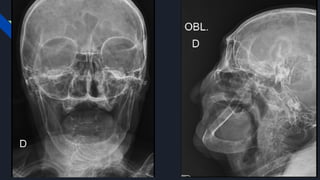

PARECER DA EQUIPE DA BUCO-MAXILO-FACIAL:

DISCUTIDO CASO COM EQUIPE DE ORTOPEDIA, PACIENTE SERÁ REAVALIADA

APÓS REALIZAÇÃO DOS EXAMES DE IMAGEM SOLICITADOS (RX DE FACE E

MANDÍBULA). ORIENTO MANEJO CUIDADOS DAS ÁREAS DAS FRATURAS EM

FACE, PRINCIPALMENTE CASO ANESTESIA SEJA GERAL, ASSIM COMO, CASO

POSSÍVEL PRIORIZAR INTUBAÇÃO ORAL E EVITAR FORÇA EM REGIÃO DE

MANDÍBULA. SEGUE EM ACOMPANHAMENTO CONJUNTO COM EQUIPE

ORTOPEDIA.

• 8.

PARECER DA EQUIPEDA BUCO-MAXILO-FACIAL: DISCUTIDO CASO COM EQUIPE DE ORTOPEDIA, PACIENTE SERÁ REAVALIADA APÓS REALIZAÇÃO DOS EXAMES DE IMAGEM SOLICITADOS (RX DE FACE E MANDÍBULA). ORIENTO MANEJO CUIDADOS DAS ÁREAS DAS FRATURAS EM FACE, PRINCIPALMENTE CASO ANESTESIA SEJA GERAL, ASSIM COMO, CASO POSSÍVEL PRIORIZAR INTUBAÇÃO ORAL E EVITAR FORÇA EM REGIÃO DE MANDÍBULA. SEGUE EM ACOMPANHAMENTO CONJUNTO COM EQUIPE ORTOPEDIA.